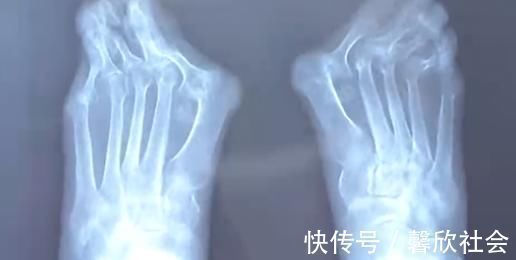

由于高跟鞋的挤压,王女士的左脚大脚趾变成了两个脚趾,随着时间的推移,大脚趾一侧又多了一个 \\\\'\\\\'拐\\\\'\\\\',现在只能通过手术来缓解症状。除了鞋子不当,遗传和疾病因素也是造成拇指外翻的原因,70 岁的高女士患风湿病,脚也发生了接近 60 度的严重变形。

忍痛十几年,直到前几天,高女士连男士的鞋子都穿不上,眼看着不能走路了才来到医院就诊,而这时手术的风险和难度都增大很多。